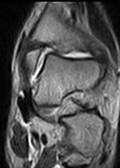

Посттравматический рассекающий остеохондрит.

Основанием для диагноза явилось выявление локальных очагов деструкции суставных поверхностей, свободных костных и хрящевых фрагментов в суставной полости. С целью уточнения распространенности процесса в костной ткани всем этим больным была проведена КТ. При этом у 11 пациентов изменения были обнаружены только в таранной кости, у 4 - в большеберцовой, а у двух больных изменения наблюдались как в таранной, так и в большеберцовой костях.

Рис 11. По переднему краю б/б и тела таранной костей (стрелка) - сигналы высокой интенсивности на Т2 (низкий - на Т1 ВИ), округлой формы, с четкими контурами и 2D реконструкция, где виден участок костной деструкции (а). |

По нашему опыту, методом выбора в диагностике РО является МРТ и не зависит от степени напряженности магнитного поля